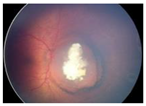

| Group Classification | Morphological Characteristics | Image of Ocular Damage |

|---|---|---|

| Group A | Small tumors (≤3 mm) confined to retina; >3 mm in fovea; 1.5 mm in optic disc | ![]() |

| Group B | Tumors (>3 mm) confined to retina, clear subretinal fluid (≤6 mm from tumor margin) | ![]() |

| Group C | Localized vitreous and/or subretinal seeding (<6 mm from tumor margin) | ![]() |

| Group D | Diffuse vitreous and/or subretinal seeding (>6 mm from tumor margin). Subretinal fluid > 6 mm from tumor margin. | ![]() |

| Group E | No visual potential and poor prognostic features; Retinoblastoma occupying > 50% of the globe, invasion of the optic nerve, choroid, sclera, orbit, anterior chamber | ![]() |